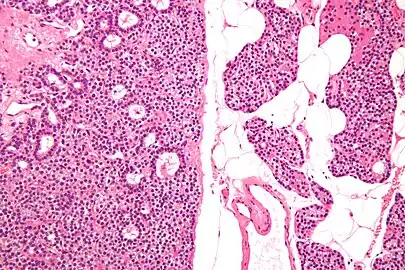

Micrograph of a parathyroid adenoma (left) and normal parathyroid gland (right). H&E stain.

Normal parathyroid gland with prominent adipose tissue is seen on the right of the image.-High magnification

Histopatholgical image of parathyroid adenoma in a patient with primary hyperparathyroidism. Hematoxylin and eosin stain.

Histopatholgical image of parathyroid adenoma in a patient with primary hyperparathyroidism. Hematoxylin and eosin stain. Another view of the same lesion